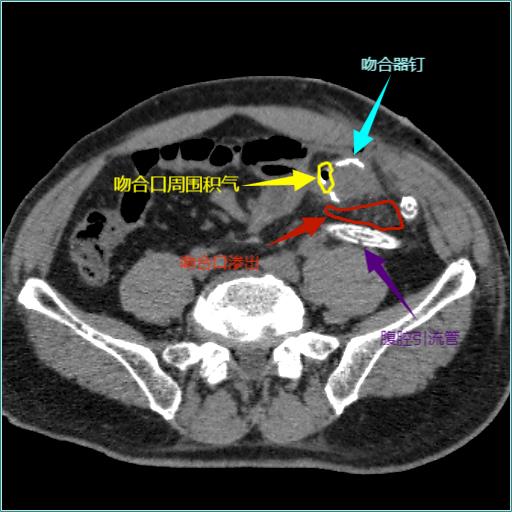

图1 结直肠手术后吻合口漏CT图像Fig.1